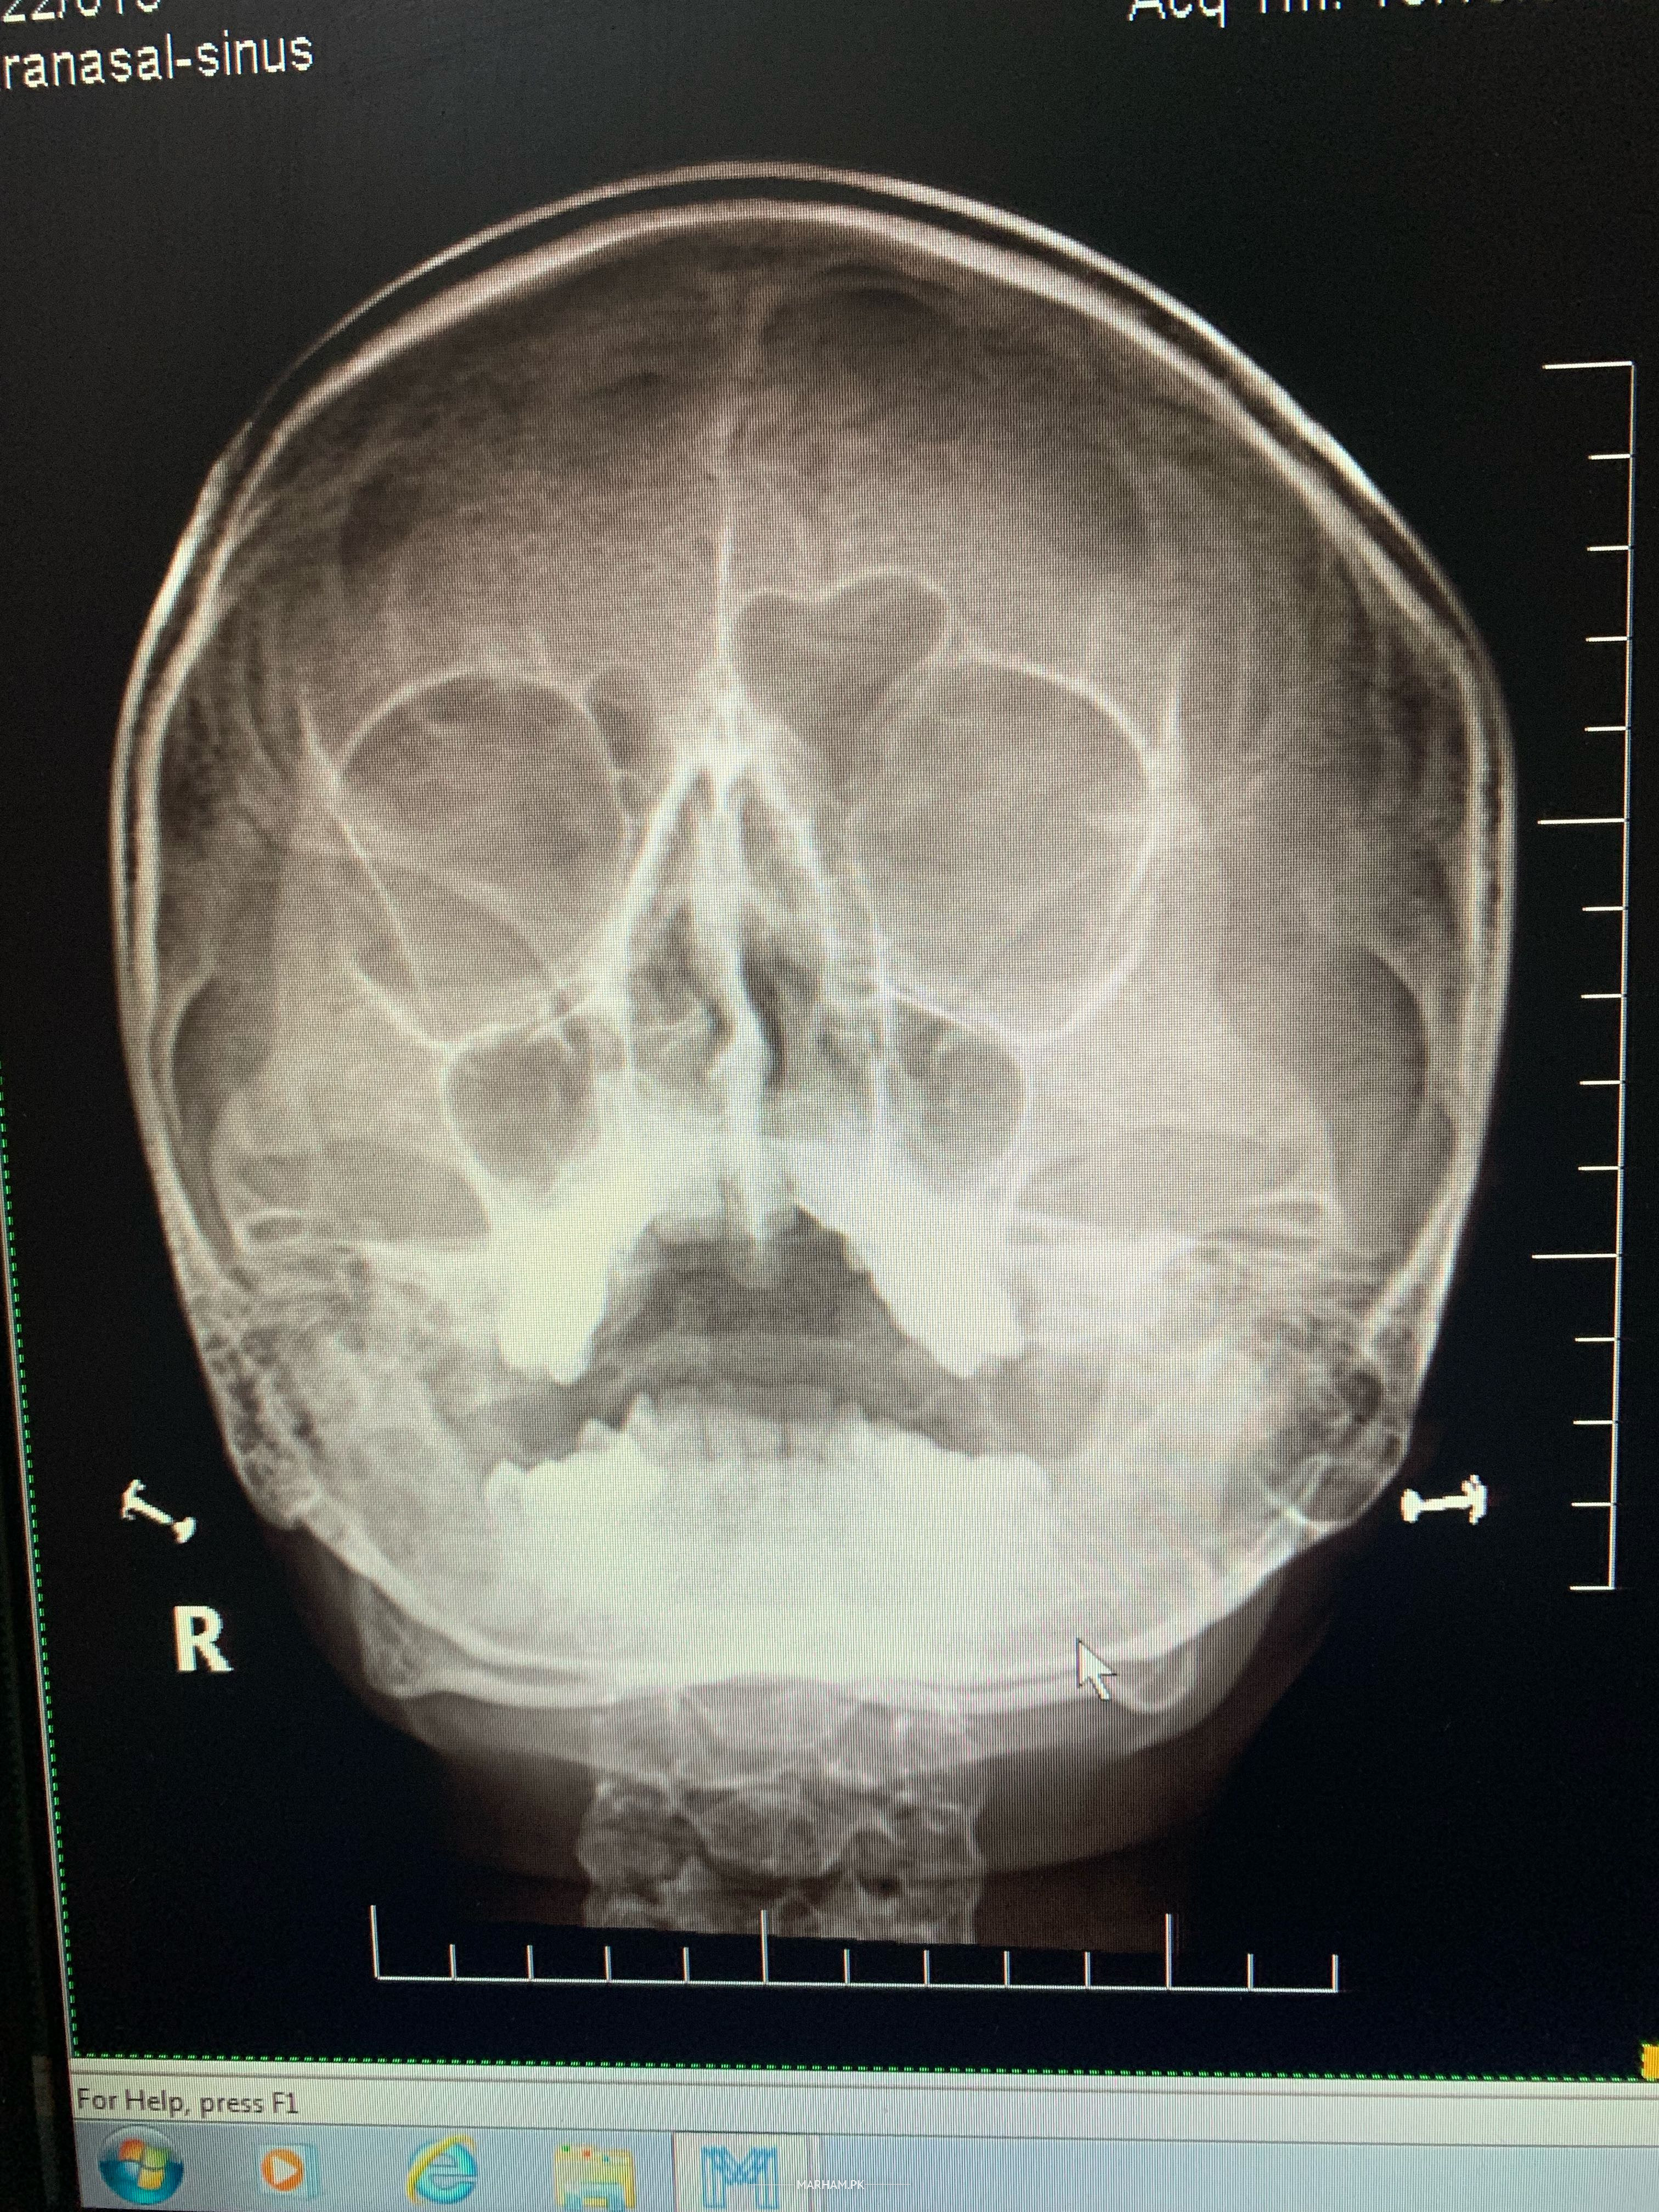

She is having difficulty in breathing. She has taken myteka, rapricot, jardin for a week and taking nose drop since 20 days Rhino Sone P prescribed by ENT doctor. But medicine doesn’t help. I’m attaching xray report. Kindly have a look. Breathing problem in night, after shower and work.

Thanks for consulting this XRay has no role nowadays, she need CT scan PNS plain then consult me in karachi or online.